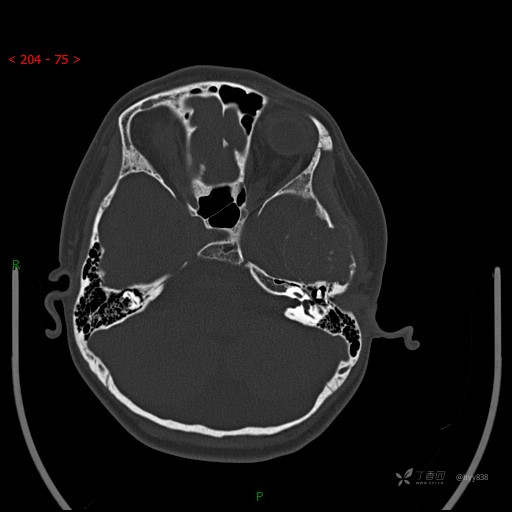

“典藏”病例分享。10岁儿童,头痛头晕一周余,CT、MRI 都有---结果公布~

简要病史:患者于一周前无明显诱因开始出现头痛头晕,无恶心呕吐,无肢体抽搐,无寒颤高热,无腹胀腹泻,无视力下降及视野缺损,上述症状休息后可稍缓解,未引起重视。 2天前患者头痛头晕不适加重,伴有恶心感,无呕吐,遂到当地人民医院行头颅CT检查示:左侧颞部占位性病变,今日家属为求进一步治疗,来我院门诊求治。门诊拟“左侧颞部占位性病变”收入我科。 患病以来,患者精神、饮食、睡眠尚欠佳,大小便如常,体力体重无明显变化。

临床诊断:左侧颞部占位

颅脑CT扫描